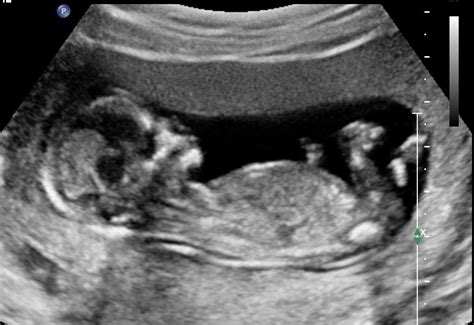

De 13-weken echo is een vrijwillig medisch onderzoek dat plaatsvindt tussen 12 weken en 3 dagen en 14 weken en 3 dagen zwangerschap. Tijdens deze echo wordt de ontwikkeling van het kindje beoordeeld en gescreend op aanwijzingen voor bepaalde lichamelijke afwijkingen, zoals een open ruggetje, hazenlip of afwijkingen aan organen.

Deze echo wordt uitgevoerd door een gespecialiseerde echoscopist met geavanceerdere apparatuur. Een voordeel van het laten uitvoeren van deze echo in de eigen praktijk is de nauwe samenwerking binnen het team, wat snelle communicatie en eventuele vervolgstappen vergemakkelijkt. De 13-weken echo wordt volledig vergoed vanuit het screeningscentrum van de regio.

De 20-weken echo, ook wel Structureel Echoscopisch Onderzoek (SEO) genoemd, vindt plaats tussen 18 en 21 weken zwangerschap. Dit uitgebreide onderzoek beoordeelt de organen, het skelet, de groei van het kindje, de placenta en het vruchtwater.

Net als de 13-weken echo is de 20-weken echo bedoeld voor screening op mogelijke afwijkingen. Indien de 13-weken echo reeds in dezelfde praktijk is uitgevoerd, wordt geadviseerd om ook de 20-weken echo daar te laten maken voor continuïteit van zorg en dossiervoering. De 20-weken echo wordt eveneens volledig vergoed vanuit het screeningscentrum van de regio.